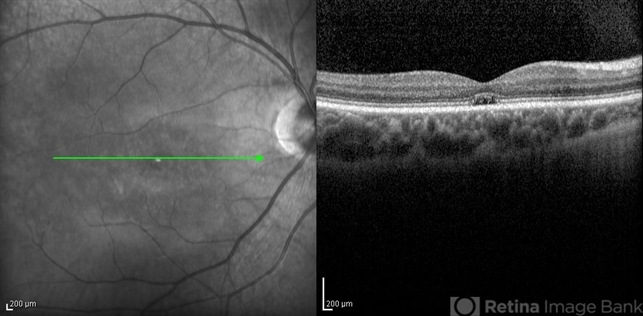

- infrared image, optical coherence tomography (OCT), cone dystrophy

Spectralis OCT - Description

- Infrared and OCT images of the right eye of a 16-year-old boy with decreased visual acuity and color vision deficiency due to cone-rod dystrophy.